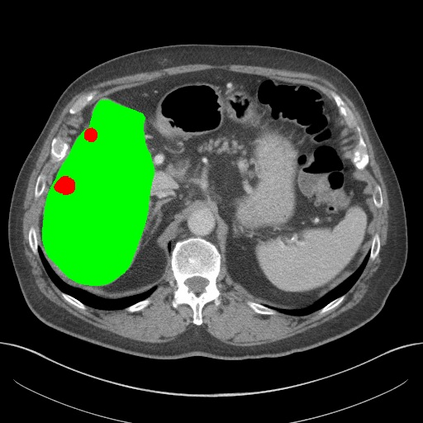

Transformers have made remarkable progress towards modeling long-range dependencies within the medical image analysis domain. However, current transformer-based models suffer from several disadvantages: (1) existing methods fail to capture the important features of the images due to the naive tokenization scheme; (2) the models suffer from information loss because they only consider single-scale feature representations; and (3) the segmentation label maps generated by the models are not accurate enough without considering rich semantic contexts and anatomical textures. In this work, we present CASTformer, a novel type of generative adversarial transformers, for 2D medical image segmentation. First, we take advantage of the pyramid structure to construct multi-scale representations and handle multi-scale variations. We then design a novel class-aware transformer module to better learn the discriminative regions of objects with semantic structures. Lastly, we utilize an adversarial training strategy that boosts segmentation accuracy and correspondingly allows a transformer-based discriminator to capture high-level semantically correlated contents and low-level anatomical features. Our experiments demonstrate that CASTformer dramatically outperforms previous state-of-the-art transformer-based approaches on three benchmarks, obtaining 2.54%-5.88% absolute improvements in Dice over previous models. Further qualitative experiments provide a more detailed picture of the model's inner workings, shed light on the challenges in improved transparency, and demonstrate that transfer learning can greatly improve performance and reduce the size of medical image datasets in training, making CASTformer a strong starting point for downstream medical image analysis tasks.